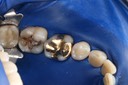

Ted Kanamori #18-19 prep